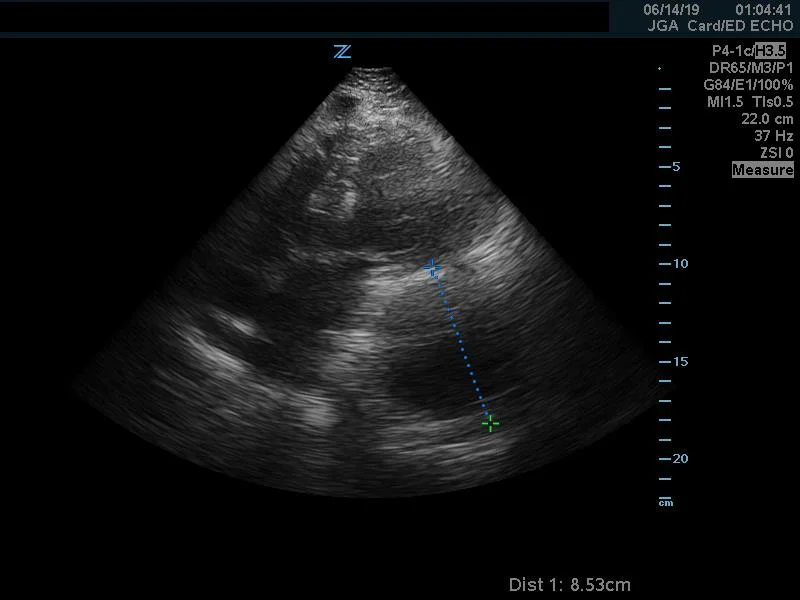

Measurement.jpg

The parasternal short view also had more important information.